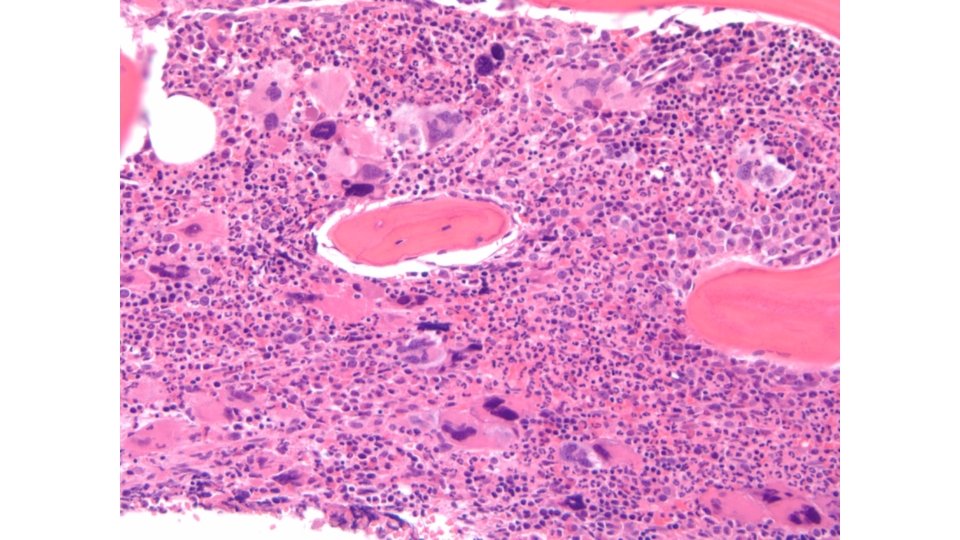

Key Features of Myelodysplastic Syndromes (MDS) Patients 2 o MDS Median age at diagnosis ~70 Prior chemotherapy (alkylators, topoisomerase II inhibitors) in 5%-10% Prior radiation Exposure in <5% Disease features >95% of patients have cytopenias, most commonly anemia; less than half have neutropenia or thrombocytopenia at diagnosis Clinical course MDS Paradox: Bone marrow usually hypercellular Cells look abnormal (“dysplastic”), Blasts may be increased Death from infection, bleeding, complications of anemia (50%) “Preleukemia” ~1/2 of patients have abnormal chromosomes on G-banded karyotyping, usually numeric anomalies Death from other causes (25%) AML (25%) Fenaux P. Semin Hematol. 2004; 41(2 suppl 4): 6 -12.

Case Study 3 • • 57 year old gentleman noted to have polycythemia on routine blood testing. He has no smoking history, no COPD or sleep apnea, no testosterone use. He had drenching night sweats, 30 LB weight loss over 2 months, and mild splenomegaly on imaging. He had one prior episode of documented TIA. Bone marrow biopsy showed mildly hypercellular bone marrow 50 -60% with atypical megakaryocytes, normal karyotype and JAK-2 V 617 F mutation detected (VAF 46%) and IDH-1 mutation (VAF 26%). Based on the patient’s test results, what would be the most likely diagnosis? A. Primary myelofibrosis (PMF) B. Polycythemia vera (PV) C. Essential thrombocythemia (ET) D. Chronic myelogenous leukemia (CML)

2016 WHO Criteria for Diagnosis of PV • WHO diagnosis of PV requires: – Presence of all 3 major criteria, or – Presence of the first 2 major criterion together with the minor criterion Major Criteria 1. Hemoglobin level > 16. 5 g/d. L in men, > 16. 0 g/d. L in women OR Hematocrit > 49% in men, > 48% in women OR Evidence of increased red cell mass 2. Bone marrow biopsy showing hypercellularity, trilineage growth (panmyelosis) 3. Presence of JAK 2 V 617 F or JAK 2 exon 12 mutation Minor Criterion 1. Subnormal serum erythropoietin (EPO) level Arber DA, et al. Blood. 2016; 127(20): 2391 -405.